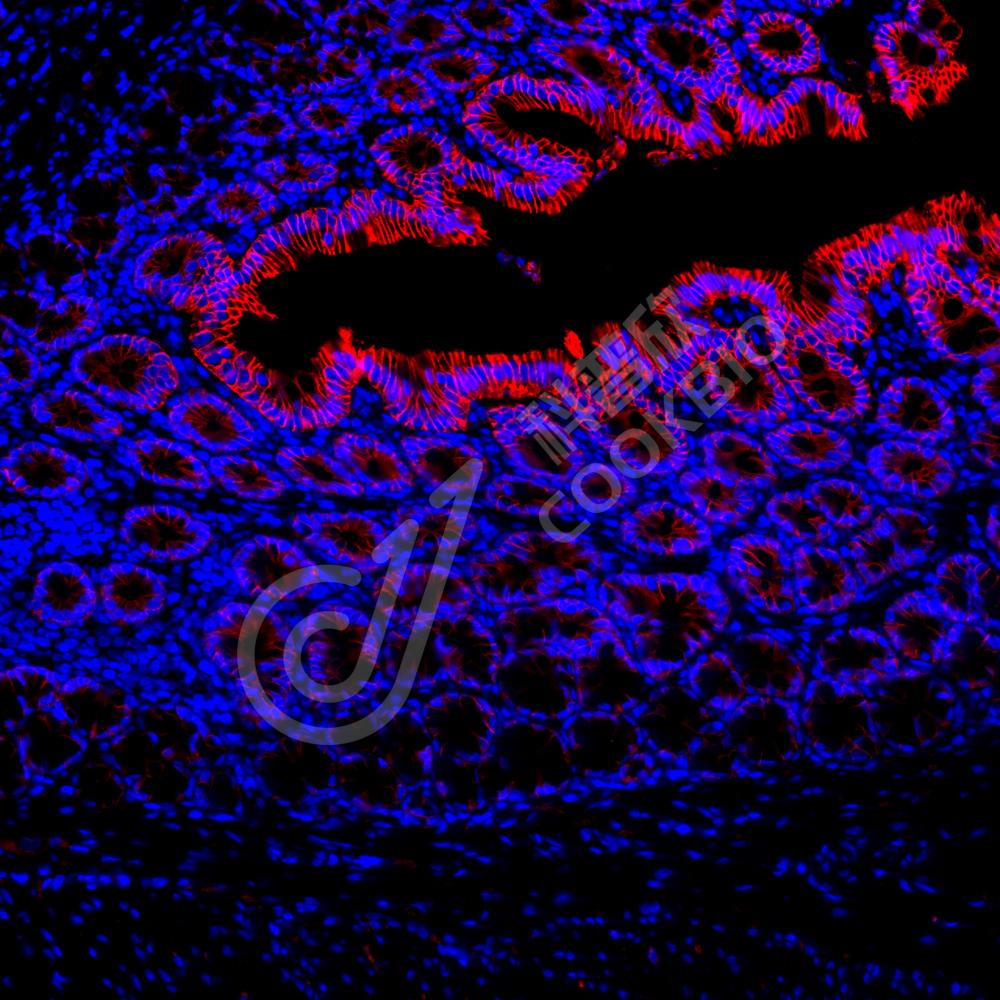

IF检测Sodium Potassium ATPase蛋白(货号 K134200-1)(红色).

样品: 大鼠结肠, 4%多聚甲醛 (货号KSG1101) 固定12-24小时.

抗原修复: Tris-EDTA抗原修复液(pH 9.0) (KSG1203), 98℃, 20分钟.

封闭: 3% BSA(货号KSGC305010)的PBS溶液, 室温孵育30分钟.

—抗: 1: 800稀释, 4℃ 孵育过夜.

二抗: Cy3标记山羊抗兔IgG (H+L) (货号KB63909), 1: 300稀释, 室温孵育1小时.